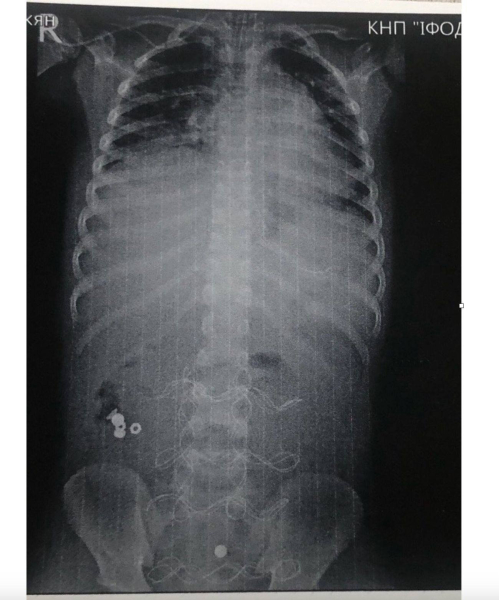

“Поділюся з вами медично складною історією з, на щастя, хорошим кінцем. До нас в ОДКЛ привезли 7-річного хлопчика у вкрай тяжкому стані інфекційно-токсичного шоку з клінікою розлитого перитоніту.

Як виявилось, все через батарейку, яку дитина проковтнула, що спричинило перфорацію тонкого кишківника”, – зазначив Тарас Мельник.

Хлопчику з Прикарпаття провели 3 операції, щоб врятувати після того, як він проковтнув батарейки

Фото: Тарас Мельник